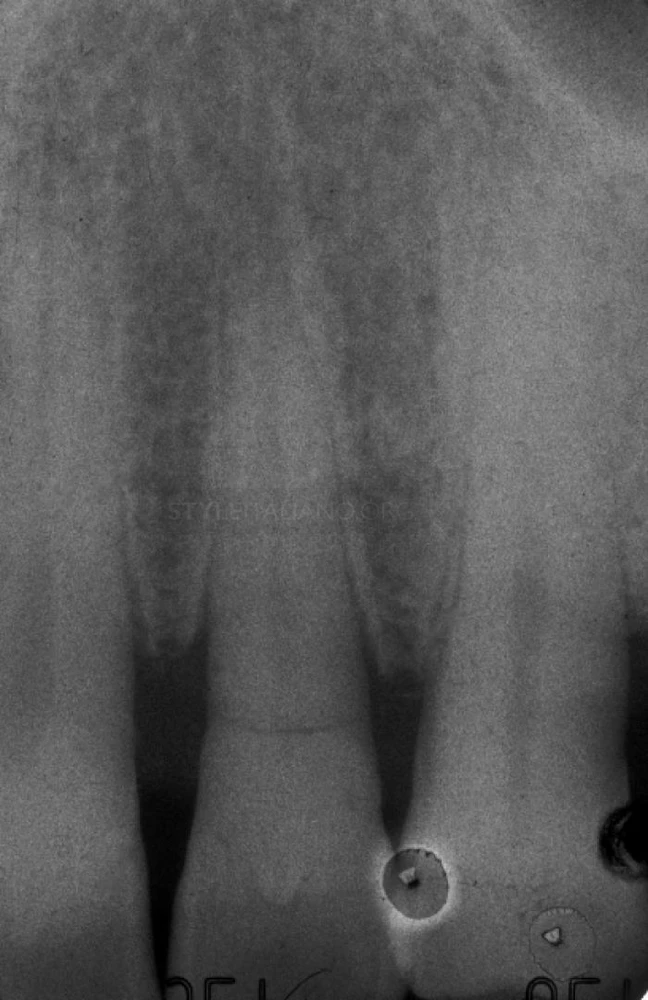

Thông qua phim X-Quang có thể thấy chân răng đã bị gãy và vị trí gãy cao hơn mào xương ổ răng, đồng thời vết gãy đã xâm nhập vào buồng bột của răng cửa bên cạnh.

Trên phim x-quang sau điều trị có thể thấy sự chắc chắn giữa gutta percha ở ống tủy, chốt sợi và đường gãy.